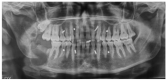

Mandibular Reconstruction after Resection of Ameloblastoma by Custom-Made CAD/CAM Mandibular Titanium Prosthesis: Two Case Reports, Finite Element Analysis and Discussion of the Technique

Virtual surgical planning for CAD/CAM mandibular reconstruction by titanium prosthesis was recently reported for resected cases. Even if some advantages are evident, difficulties that may arise for TMJ function after reconstruction originate from prosthesis contamination through oral mucosa dehiscence. In these two cases reported of mandibular reconstruction after resection of ameloblastoma by custom-made CAD/CAM titanium prosthesis, the procedures were aimed to preserve the TMJ glenoid cavity and articular disc avoiding functional problems for hemi-mandibular resections that included the condyle (as in case #1) or with condylar preservation (as in case #2) and avoiding intraoral incisions in both cases. The entire surgical planning and prosthetic fabrication were explained with specifications and the sequence of the surgical procedure. Finite elements analysis (FEA) was performed to check the force distribution and efficacy of the prosthetic device (case 1 with hemi-mandibular resection and rehabilitation). Although successful in these two cases, surgical reconstruction of the mandibular defect after resection by a CAD-CAM custom-made prosthesis still shows some drawbacks and failure risks. Several advantages of this technique and the surgical success in these two cases were presented, but limitations and side effects must be considered when cases are selected.